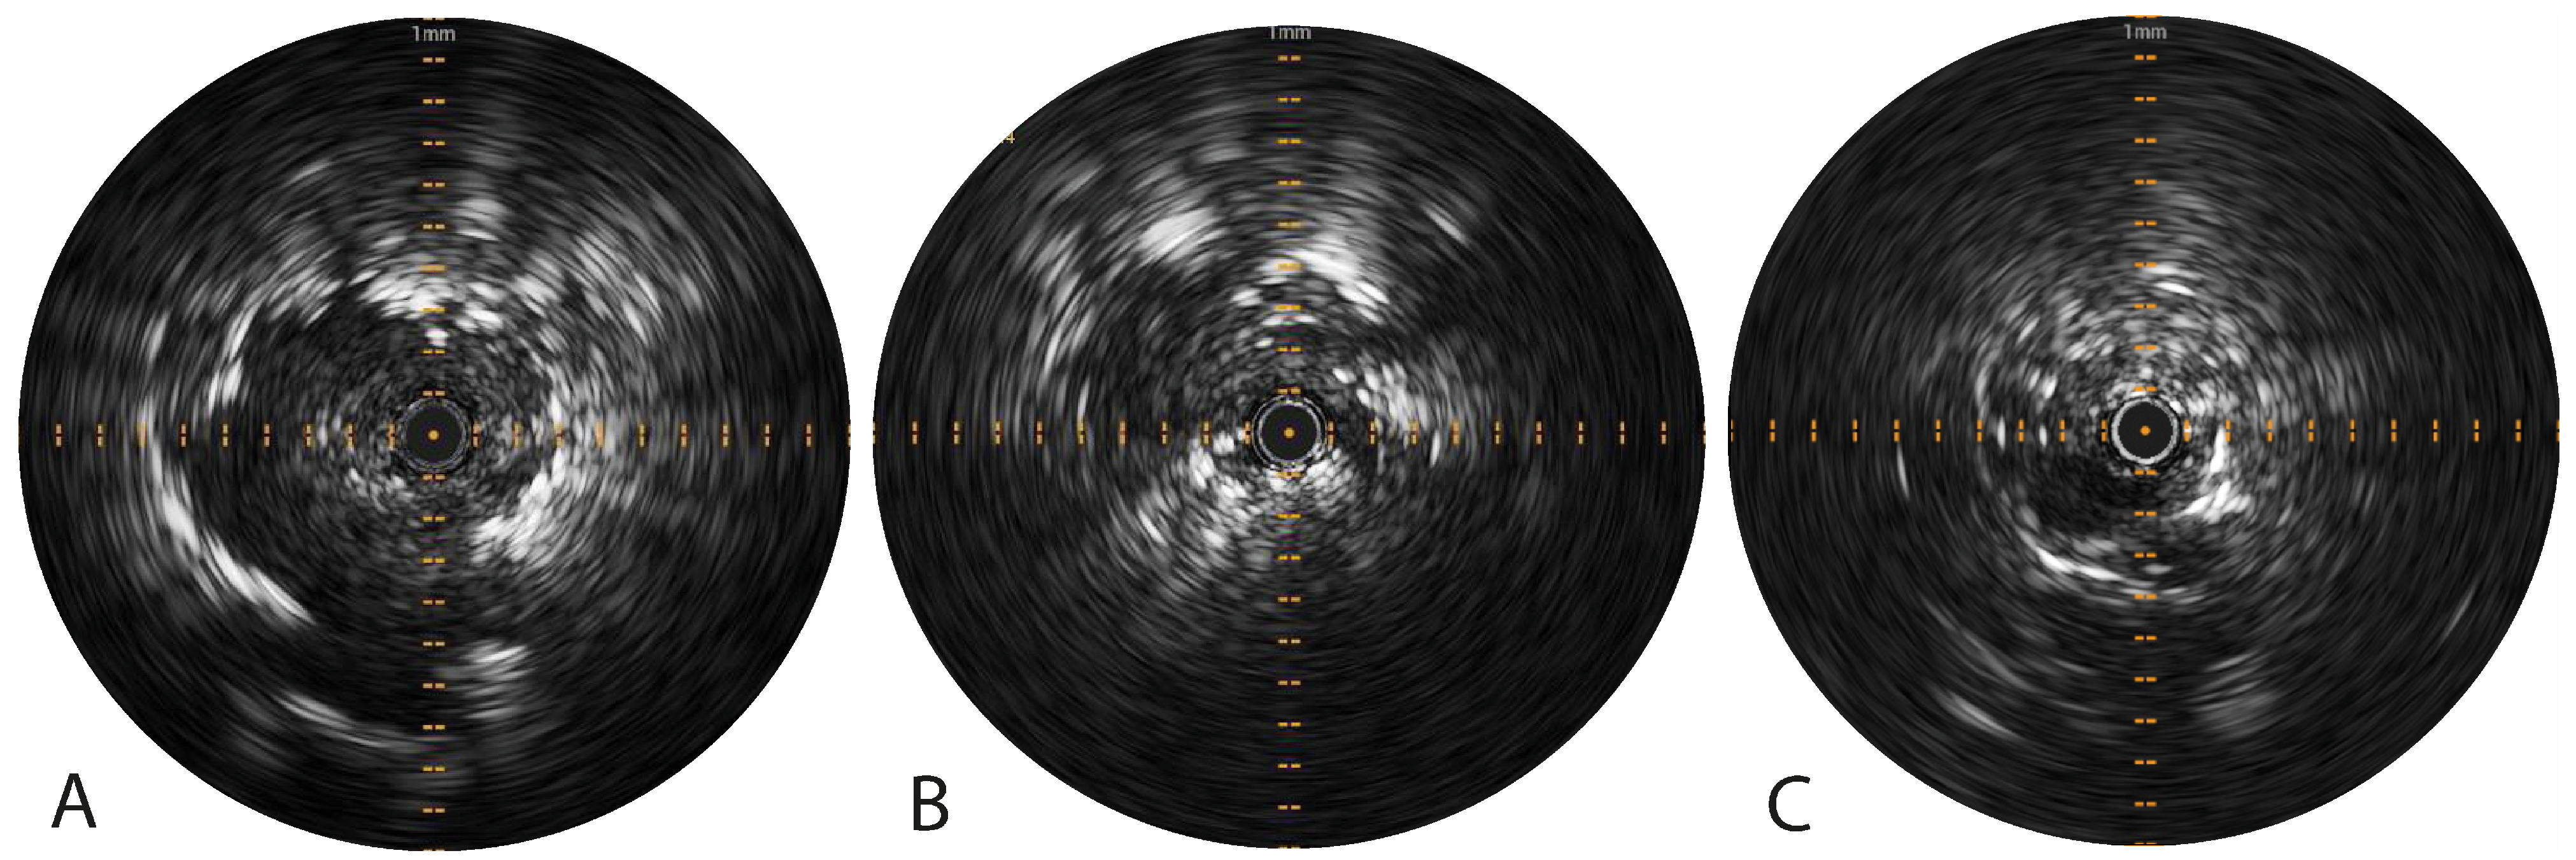

3.1. Pioneer Plus Radial Ultrasound

| Tumor visibility on radial US imaging, n (%) | 29 (96.7%) | ||

| Real-time radial US visibility of tracer injection, n (%) | 0 (0.0%) | ||